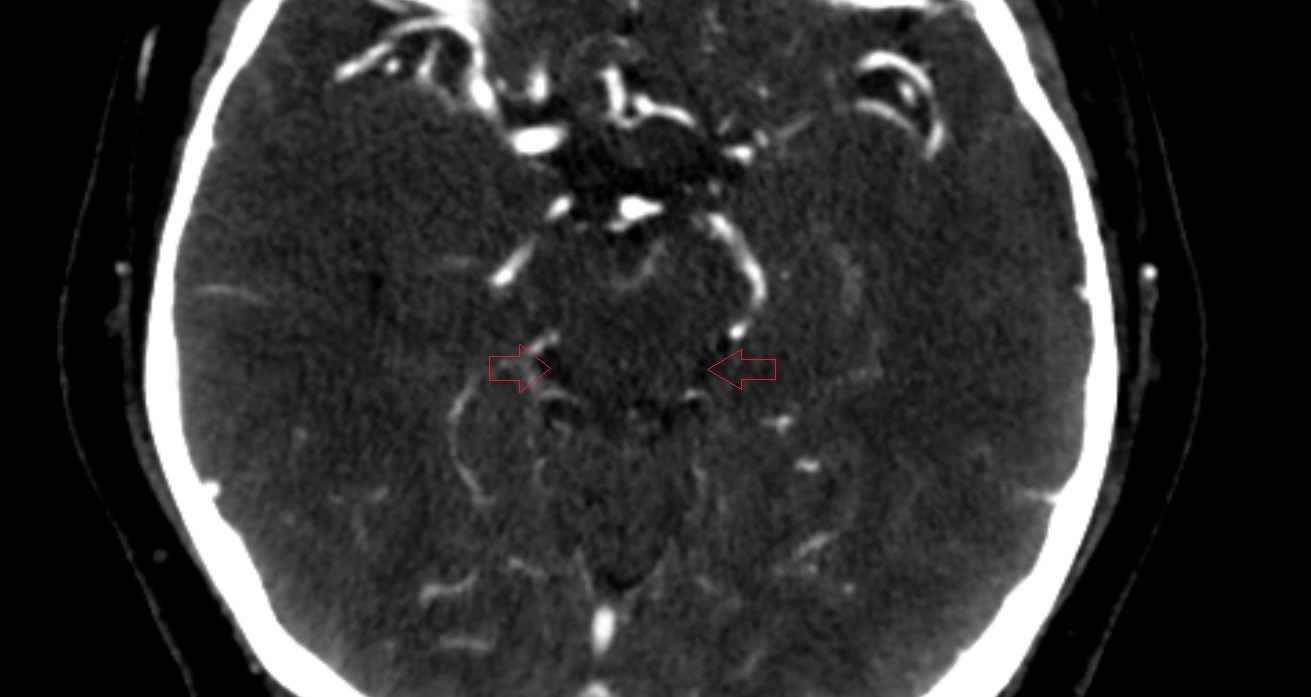

- Lateral aperture of fourth ventricle (foramen of Luschka)

- Lateral aperture of the fourth ventricle

- Lateral recess fourth ventricle

- Cerebellopontine cistern

- Pontocerebellar cistern